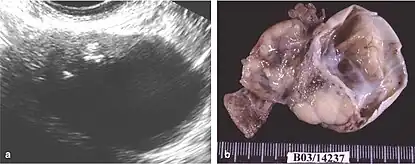

Although the majority of MCT cases are non-malignant, approximately 0.17-2% may undergo malignant transformation, with squamous cell carcinoma being the most prevalent, constituting 80% of such transformations.[11] The clinical presentation of oSCC development within MCT lacks specificity, often resulting in the inadvertent discovery of early-stage tumors during routine examinations or postoperative assessments. In advanced cases, patients may exhibit palpable masses, abdominal swelling, and pain, potentially leading to acute abdominal complications due to tumor involvement.[10][12][4]

Similar to other ovarian cancers patients can undergo a series of tests to identify characteristics and/or markers. This test includes a pelvic exam, imaging (CT, MRI, ultrasound), blood test, and in some cases biopsy with histopathology. Diagnosing this condition remains challenging as preoperative imaging and laboratory tests lack specific indicators.

The difficulty in screening for SCC revolves around the creation of effective strategies with a positive predictive value. The timing aspect is crucial due to the lack of a specific timeframe for the onset of invasive disease or the interval stage between stage I and stage III carcinomas.[17] Ultrasound screening provides a detailed view of the ovaries, identifying morphologic changes as potential signs of malignancy. Key diagnostic factors include the presence of abnormalities, ovarian size, blood flow, and abdominal/pelvic fluid. The persistence of abnormalities after four to six weeks may decrease the occurrence of false positives. Screening protocols, often based on morphologic indices, utilize transvaginal ultrasound findings like cyst wall structure, septation, papillary projections, echogenicity, and ovarian volume to effectively detect malignancy.[17]